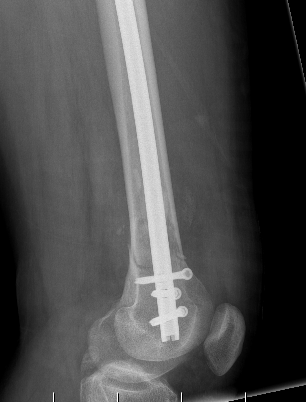

Type C: Complete articular

Xray / CT

Dual Plate

Plate + Retrograde nail

Indications

Significant comminution

Loss of medial cortical buttress

Plate + Nail